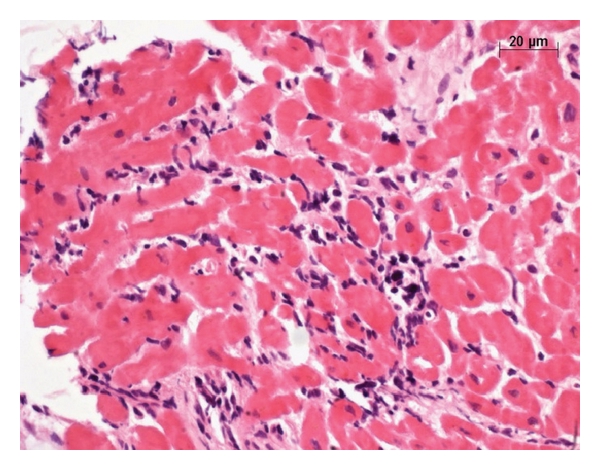

During the study period, 436 adult heart transplants were performed, and six patients (1.3%) developed T. gondii infection/reactivation in the postoperative period. All infections/reactivations occurred before 1996, and none of the patients received pyrimethamine prophylaxis. Demographic and clinical information are described in Table 1, and examples of histological examination are in Figures 1 and 2. All patients were seronegative for Chagas’ disease. Two patients (33.3%) presented with disseminated toxoplasmosis infection, and all patients (100%) had myocarditis. Five patients (83.3%) were Toxoplasma seronegative before transplant and one patient did not have before transplant serology available. Median time for Toxoplasma infection onset was 131 days (mean = 69 days, range 21–534) following transplantation. No seroconversion was detected. Three patients (50%) died due to toxoplasmosis infection. After 1996, we did not observe any additional cases of T. gondii infection/reactivation.

Endomyocardial biopsy (EMB) is a reliable way to identify and track rejection following heart transplantation, and in some cases, EMB may show the presence of infectious organisms, including Toxoplasma pseudocysts. Moreover, Toxoplasma is one of the most commonly opportunistic organisms diagnosed on EMB [7]. Toxoplasma-related myocarditis has a fugacious exudative or neutrophilic component occurring when the myocyte ruptures following Toxoplasma proliferation. This fugacious component becomes mononuclear shortly after rupture, which results in an increasingly difficult differential diagnosis of rejection. Therefore, in some cases, the lymphoid infiltrate may not be caused by transplant rejection. In addition, the pseudocysts are often present in non-inflamed myocardial tissue, that is, when there is no myocyte rupture and the microorganism remains hidden from the immune system and may go unnoticed, even by a very experienced pathologist. This occurred in one case in our series of patients, where the review of a biopsy showed a small Toxoplasma pseudocyst present in a non-inflamed area of the myocardial sample. The use of T. gondii immunohistochemistry could help with the differential diagnosis of seronegative patients with suspected acute rejections (Figures 1 and 2). Consequently, we would like to caution the pathologist to be careful in their interpretation of tissue samples, considering the difficulty in visualizing Toxoplasma pseudocysts, as well as the difficulty in differentiating the diagnosis of rejection when inflammation is induced. In our series, five of six Toxoplasma infection presented as cardiac failure without fever. In the first months following cardiac transplant, this clinical situation could be misdiagnosed as acute rejection, resulting in increased immunosuppression and inadvertent favor of T. gondii infection.